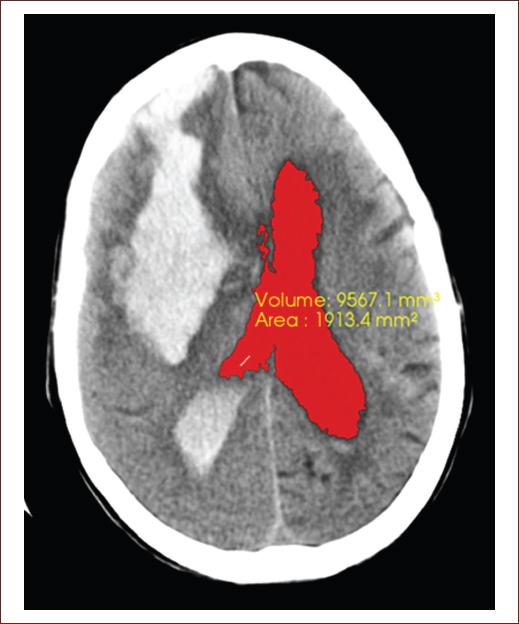

In current times, medical images have become an essential tool in clinical practice since it allows early detection of pathologies (Fig. 3). With such tools, decisions are made in real-time or photographs and samples are taken for diagnosis and recommended therapy. Other applications not only refer to medical diagnosis but also to medical planning, development and subsequent evaluation of surgical and radiotherapy6,32-34. The 80s marked the emergence of a new type of technology related to medical services, the image archiving and communication system (picture archiving and communication system [PACS]), which represents hardware and software systems, consisting of a digital network, capable of storing, exchanging and view medical images34.

Figure 3 Computed tomography image of the simple skull of an 82-year-old patient, with neurologic focalization signs related to full down, showing a recent hemorrhagic focus of 82 right front parietal HU, measuring 93.6 mm × 41.1 mm that floods the ventricular system, note the blood content in both occipital horns a predominance of the right side, associated with perilesional edema that clears the cerebral sulci at that level, collapsing the right frontal horn and compressing the body of the right lateral ventricle, which displaces the midline to 8 mm to the left. The segmentation of the lateral ventricles was performed, getting the volume 9988.4 mm3 and area 1977.7 mm2 obtained in this tomography slice (source: taken from the Imaging Department, Juan Bruno Zayas Alfonso Hospital).